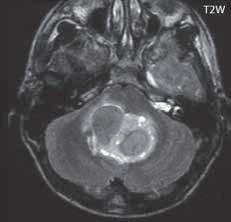

Obr. I.1.8e Dandy-Walkerovo spektrum (hypoplazie vermis, IV komora je rozšířená a široce zeje) (snímky zapůjčeny z archivu as MUDr J Lisého, CSc )

Obr. I.1.8f Dandy-Walkerovo spektrum (hypoplazie vermis, IV komora je rozšířená a široce zeje) (snímky zapůjčeny z archivu as MUDr J Lisého, CSc ); stejný pacient jako na obr I 1 8e

Obr. I.1.8g Dandy-Walkerovo spektrum (hypoplazie vermis, IV komora je rozšířená a široce zeje), (snímky zapůjčeny z archivu as MUDr J Lisého, CSc ); stejný pacient jako na obr I 1 8e, f